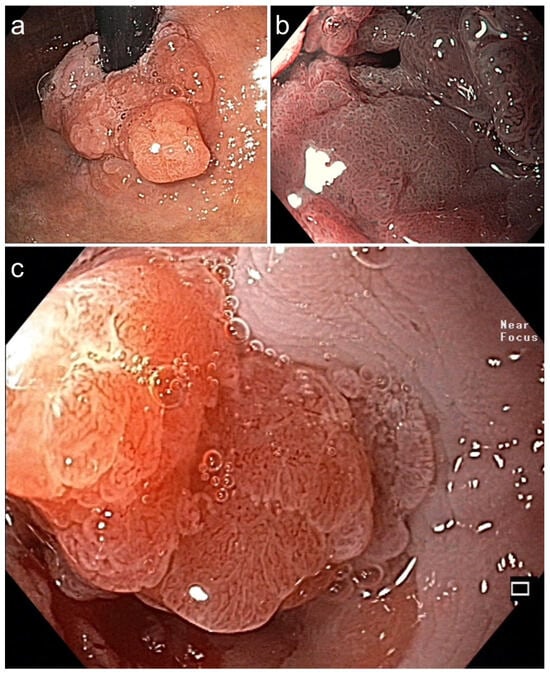

Figure 4. (a,b). Barrett adenocarcinoma 0-IIa+Is, semicircular (size 2.5 × 2 cm) in the cardia for diagnostic ESD (EUS uT1m uN0), standard WLI in prograde (a) and retroflex view (b). (c,d) A small area (0.5 cm) on the base of 0-Is with irregular SP and V/S discordance ((c) WLI 60×, (d) NBI, 60×). (e) pm-muscle retracting (MR) sign [36]. (f) Section (HE stain 100×) of AC margin showing pm invasion and resection R1 (right lower end): AC G2, pT2, R1. (Supplementary Table S3, no. 5).